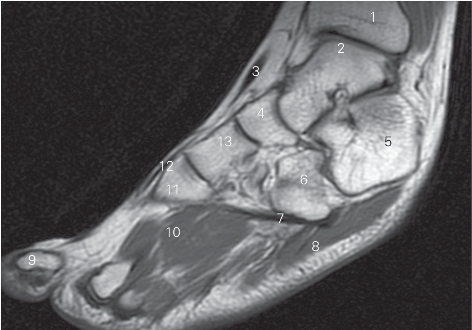

图5-58 经踝关节外踝的矢状断层MR T1加权图像

1 趾长伸肌 extensor digitorum longus

2 腓骨长、短肌 peroneus longus and brevis

3 外踝 lateral malleolus 4 距下关节 subtalar joint

5 跟骨 calcaneus 6 跟骰关节 calcaneocuboid joint

7 骰骨 cuboid bone 8 趾短屈肌 flexor digitorum brevis

9 骨间背侧肌 dorsal interossei 10 第三楔骨 3rd cuneiform bone

11 外侧楔骨 lateral cuneiform bone 12 足舟骨 navicular bone

13 距骨 talus 14 踝关节 ankle joint

15 胫骨 tibia

图5-59 经内踝管的足冠状断层MR T1加权图像

1 胫骨 tibia 2

长屈肌 flexor hallucis longus

3 趾长屈肌 flexor digitorum longus 4 跟骨 calcaneal

5 趾短屈肌 flexor digitorum brevis 6 第一跖骨 1st metatarsal bone

7 足底肌 sole muscle 8 胫骨后肌 tibialis posterior